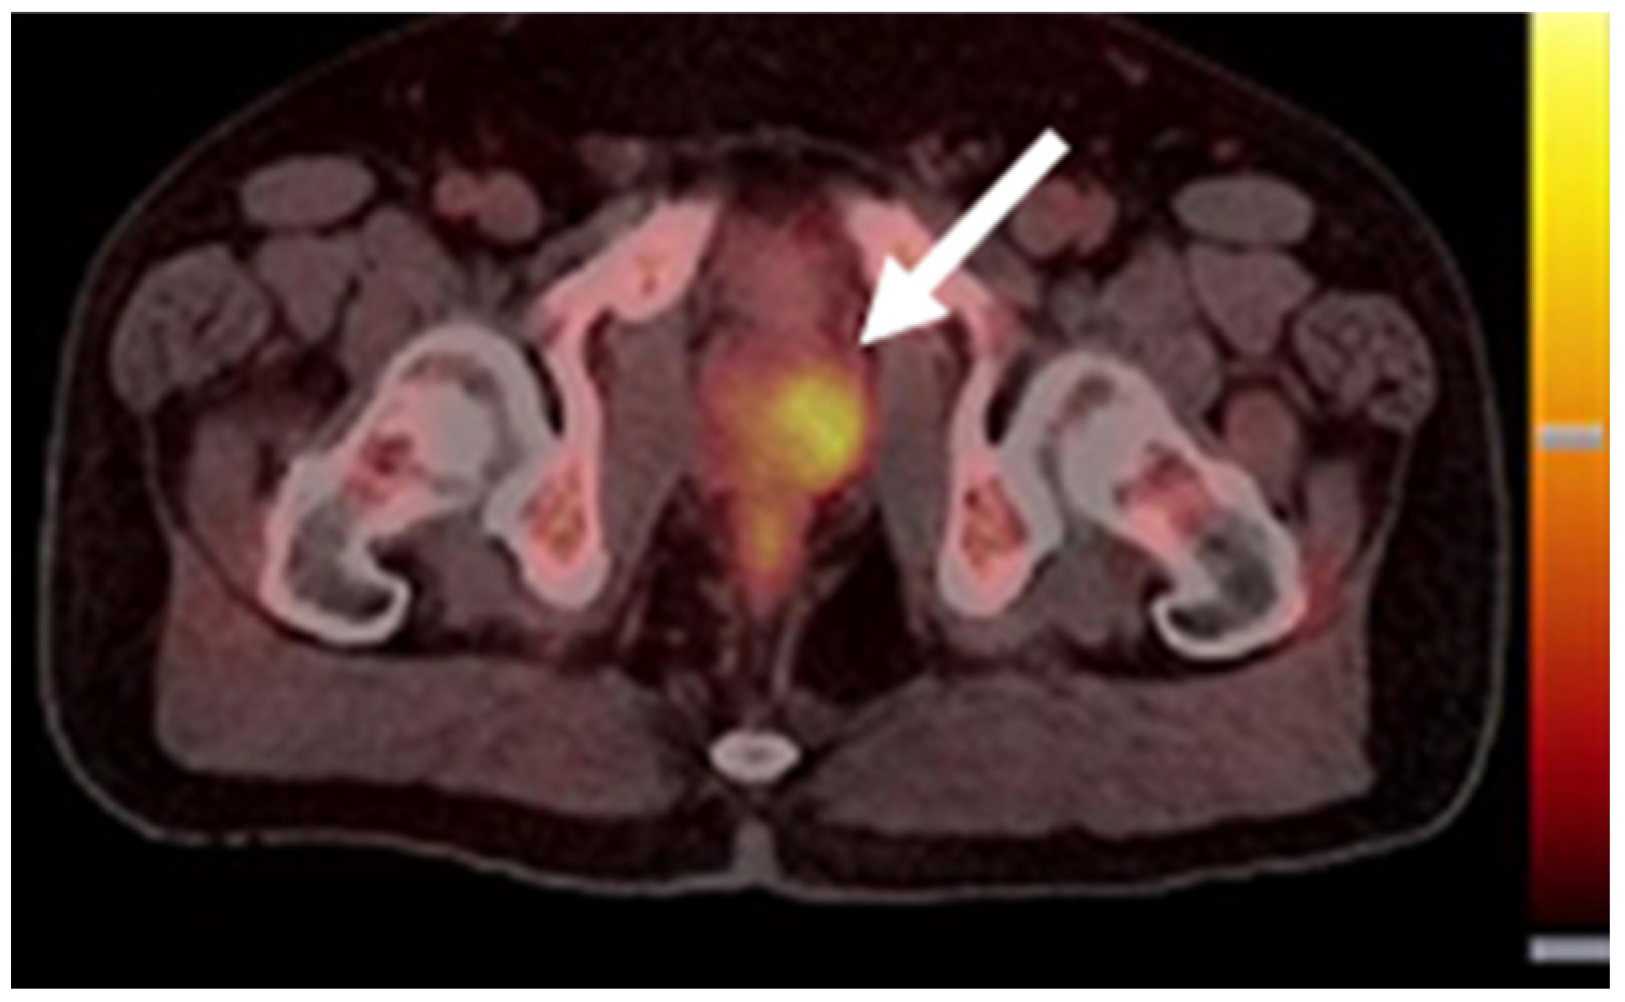

The development of PCa-specific imaging agents evolved rapidly. One particular group of tracers with the potential for PCa detection is that of the bombesin receptor antagonists, which target the GRPR. Despite the lower overall proportion of PCa exhibiting GRPR expression versus PSMA, the overexpression of GRPR is already found in primary tumors, while PSMA expression increases with PCa progression [120,121]. The bombesin receptor antagonist [68Ga]Ga-RM2 revealed PET/CT scan results that were similar to those using [68Ga]Ga-PSMA-11 in a small group of PCa patients (Figure 8) [122]. Moreover, compared with [68Ga]Ga-PSMA-11 (which accumulated in the salivary glands, lacrimal glands, and small intestine), the physiological uptake of [68Ga]Ga-RM2 was limited to the pancreas. [68Ga]Ga-RM2 could also provide more information about the retroperitoneal lymph nodes than the PSMA-targeted tracer. GRPR-targeted imaging agents may be a supplementary tracer for PSMA-negative patients.

Figure 8. [68Ga]Ga-RM2 (left) vs. [68Ga]Ga-PSMA-11 (right) PET/CT images of PCa lesions (red arrows) in a patient with LNM. This research was originally published in the Journal of Nuclear Medicine (JNM) [122].